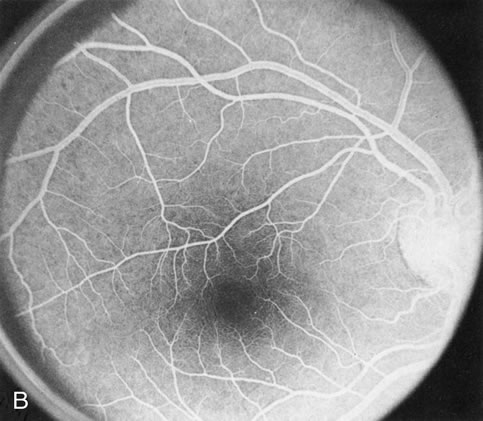

In the early stages of choroideremia, before choroidal atrophy is funduscopically obvious and when the picture resembles RP, FA indicates diffuse choroidal atrophy throughout the entire retina. Only the macular area remains preserved (Fig. 4A and B).

Fig. 4. Choroideremia and choroideremia carrier. A. The choroidal atrophy in this affected male is not apparent in the fundus. B. However, the angiogram shows diffuse atrophy of the choriocapillaris with persistent visualization of the larger choroidal vessels. C. This carrier female has peripapillary choroidal atrophy and diffuse pigment mottling. D. The patchy areas of focal choroidal atrophy that occasionally occurs in carriers is evident on angiography.

The typical carrier female, with focal or diffuse pigment mottling, does not show choroidal atrophy. However, a few carrier females have a more severe form with focal areas of choroidal atrophy. The presence of these areas, and possible progression, can be documented by FA (Fig. 4C and D). These carriers exhibit a mosaicism, which is explained by the Lyon hypothesis of random X-chromosome inactivation.